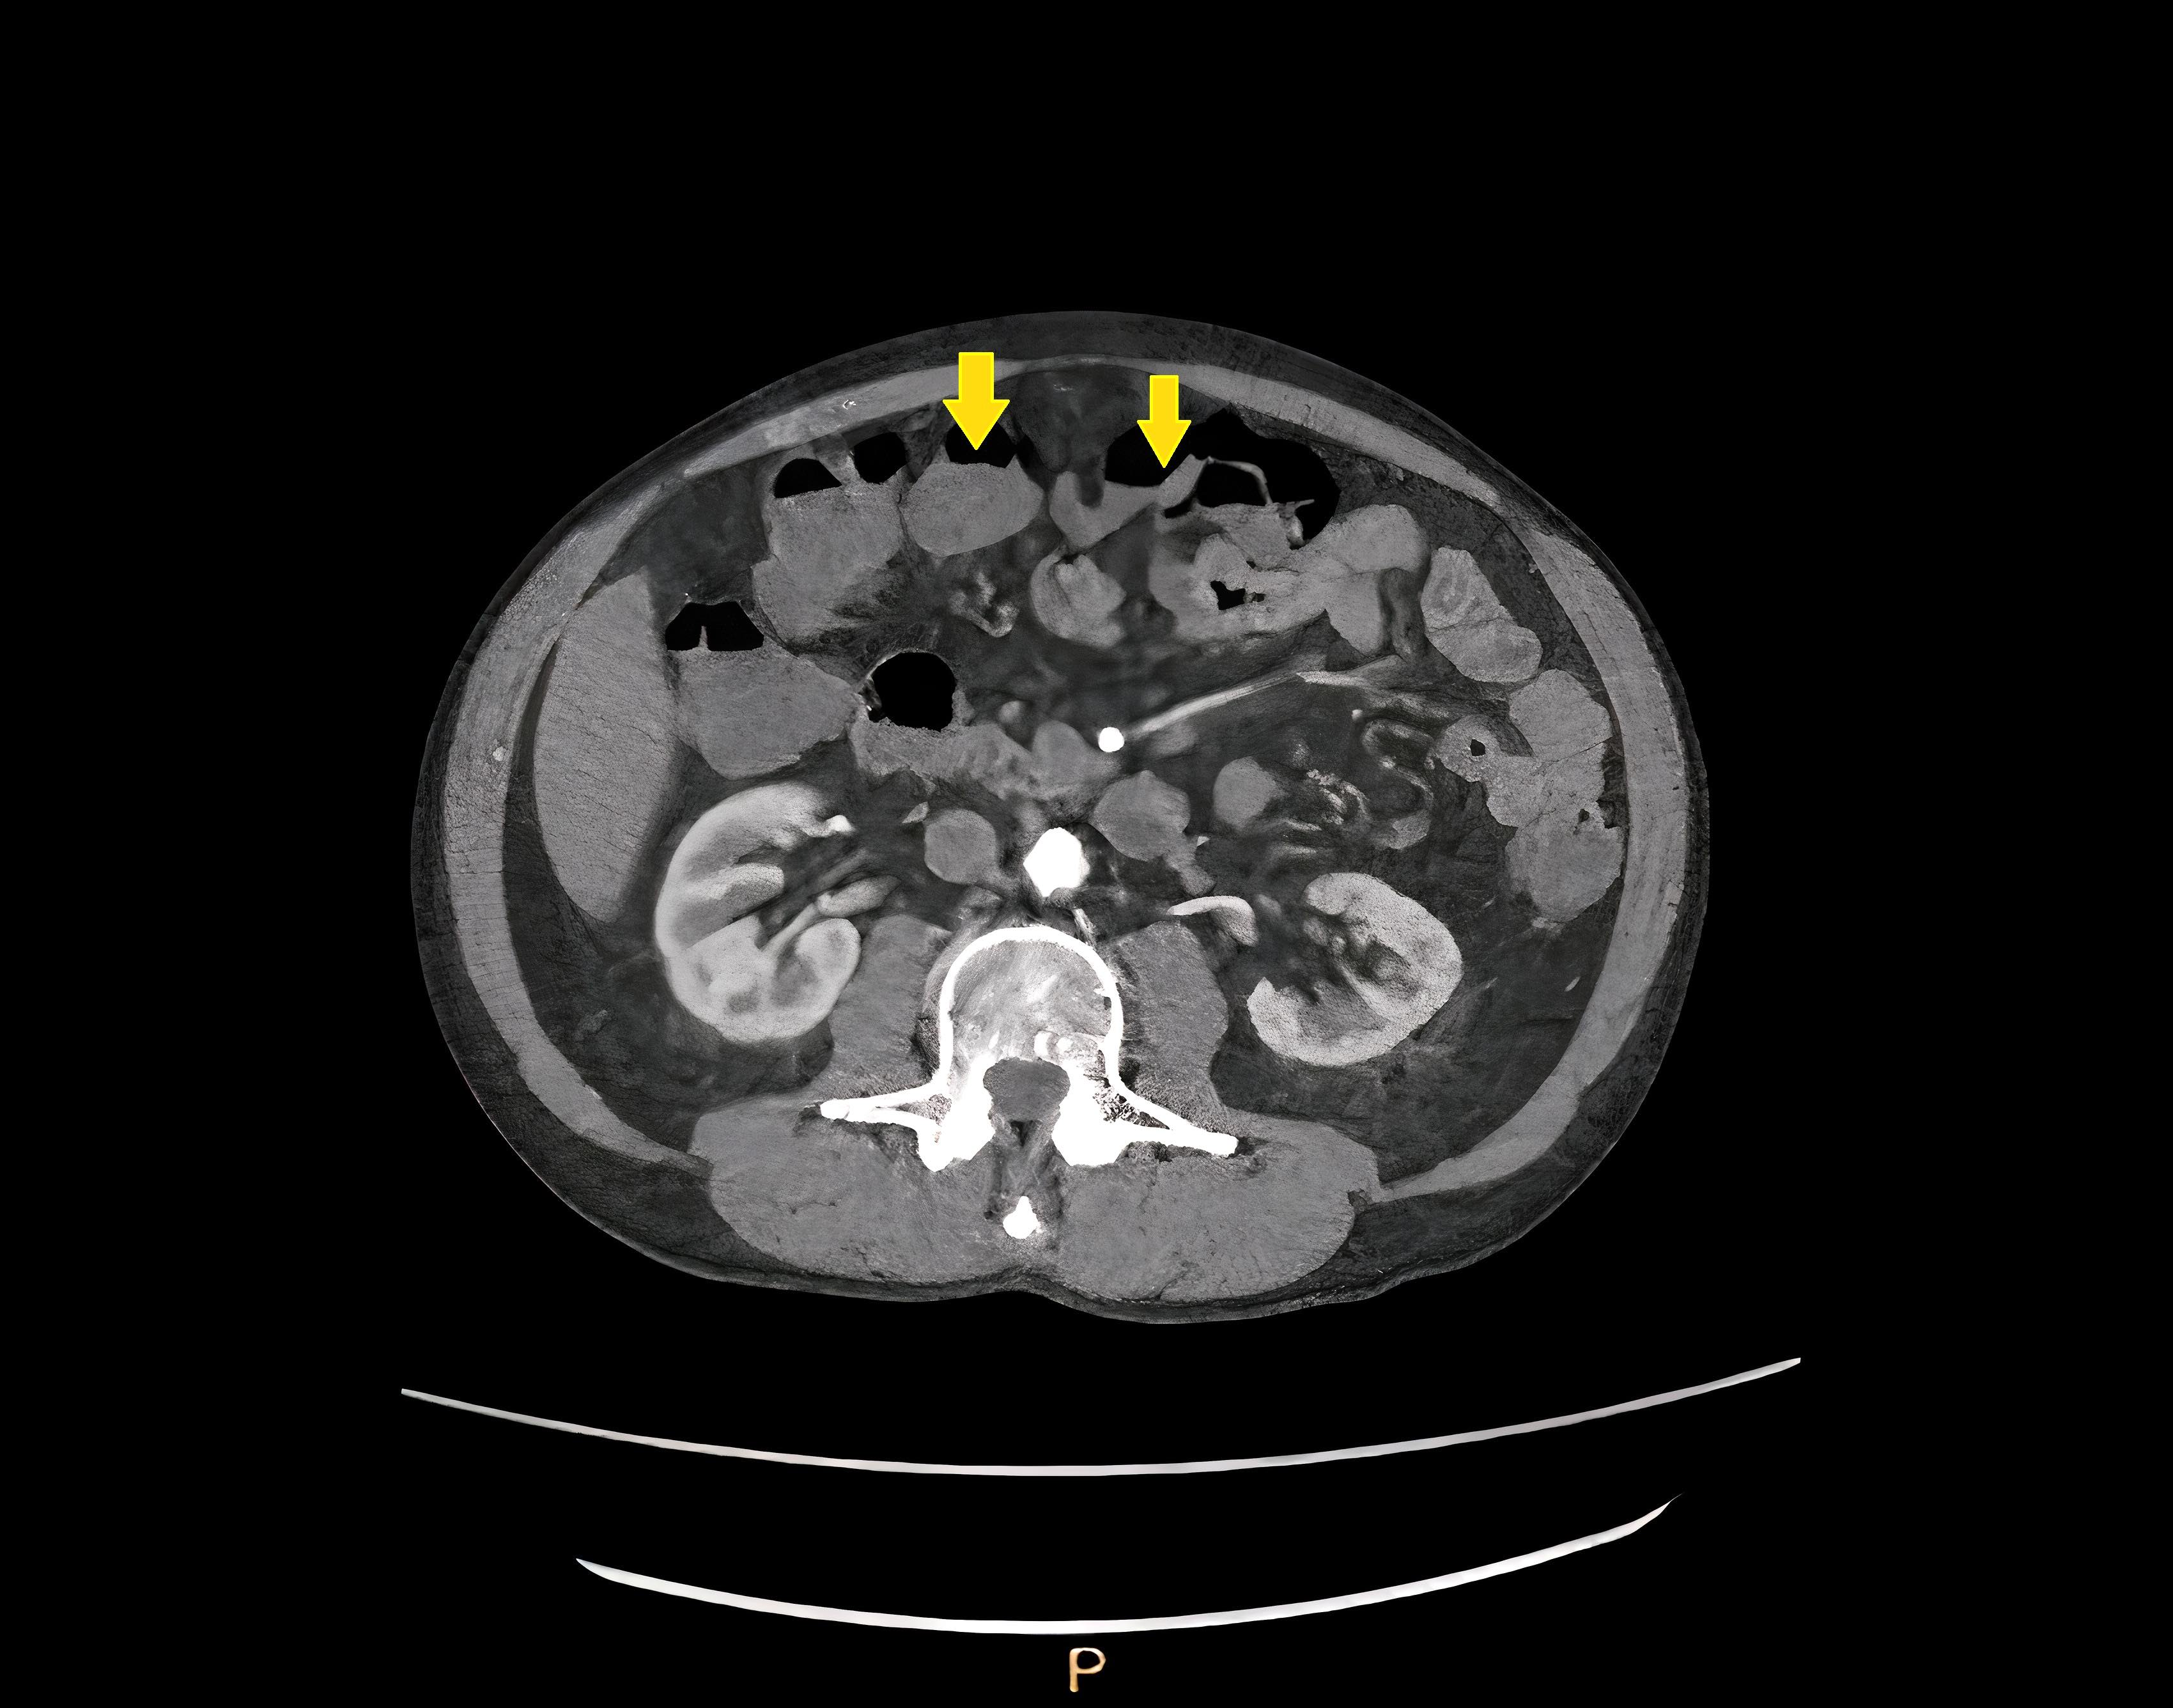

Radiology description

- Barium enema: barium filled outpouchings; can look similar to polyps

- Ultrasound: gas filled outpouchings

- CT: diverticula outlined by gas

- Intramural diverticula seen as a tiny focus of gas or contrast within the colonic wall (J Clin Gastroenterol 2004;38:S11)

- CT allows grading of severity and detection of complications (Br J Radiol 2020;93:20200670)

Radiology images